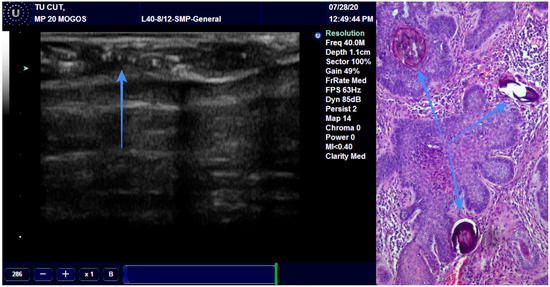

We found a very high correlation between the ultrasound measurement of the surgical margins and pathological reports, with the best result being achieved with the 13 MHz transducer, followed by the 20 MHz and 40 MHz transducers (Figure 8) (Table 5).

Figure 8.

Surgical margins measurement by US and histopathology.

Regarding the role of US in the treatment of NMSC, few studies concluded that US can easily detect malignant involvement of the margins. This may play a role in the treatment of skin cancer and prevention of local recurrence, providing improved overall survival rates. The adjacent normal tissue is measured from the limit of the tumor to the surgical resection margin. It can be easily measured on grayscale examination or elastography [44,45]. Our findings regarding the evaluation of surgical margins postoperatively illustrate the utility of this technique for immediate measurement of surgical margins directly in the operating room. All three transducers (13, 20 and 40 MHz) have shown very good results, but the most accurate was the 13 MHz transducer. This can be explained by how the lower the frequency, the deeper or greater penetrance a sound wave has. If positive or close margins are visualized, the surgery can be completed immediately. This way, the surgeon can avoid insufficient resection of the tumor or unnecessary sacrifice of healthy tissue. All these should reduce the recurrence rate and improve overall survival, but further studies are necessary to ascertain this fact.